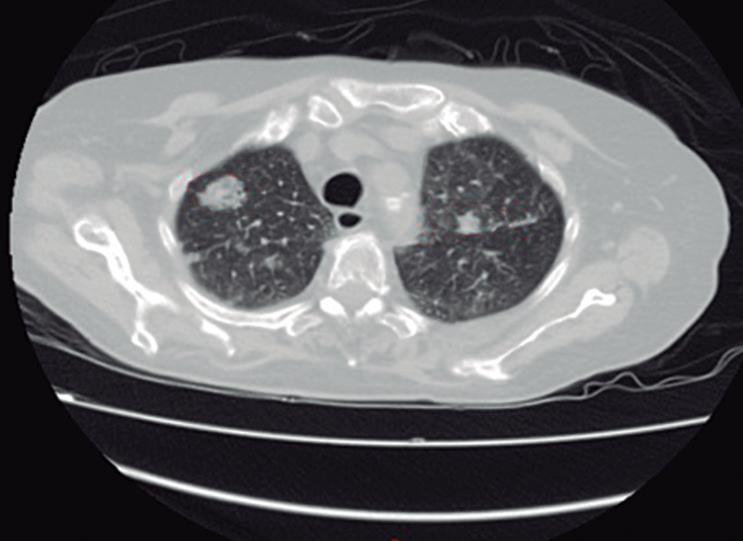

Evaluación de un paciente con dolor epigástrico y hallazgos sincrónicos infrecuentes

Roy López Grove, Daniela Soloaga, Juan Carlos Spina

Roy López Grove, Daniela Soloaga, Juan Carlos Spina 398